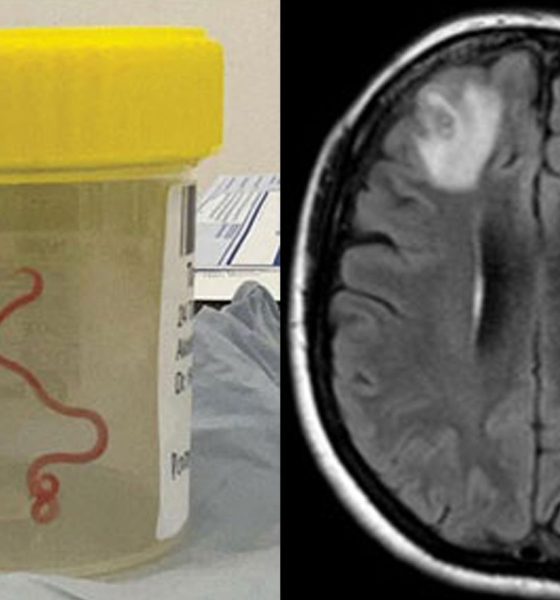

Asaj i është hequr një krimb parazitar 8 cm i gjatë.

UBT newsNjë gruaje që po përjetonte harresë dhe depresion i është hequr një krimb parazitar 8 cm i gjatë nga truri i saj.

Ndërhyrja kirurgjikale u bë alternativa e vetme dhe mjekët hoqën me sukses krimbin, i cili ishte 8 cm në gjatësi dhe 1 mm në diametër.

Rasti është i paprecedentë në historinë mjekësore dhe është dokumentuar në revistën e Sëmundjeve Infektive në zhvillim.

Profesionistët mjekësorë dyshojnë se gruaja gëlltiti pa dashje vezë krimbi duke ngrënë barëra që ishin të ndotur me feçe gjarpri, megjithatë, shkaku i vërtetë ende nuk mund të konfirmohet.

Pasi vezët çelën brenda trupit të saj, mjekët besojnë se larvat nisën një udhëtim drejt trurit të saj. Kjo mund të ishte ndikuar nga ilaçet që ajo merrte, të cilat komprometuan sistemin e saj imunitar./UBTNews/